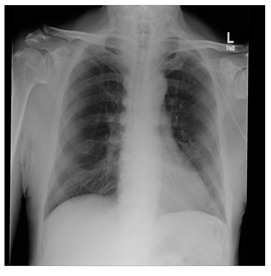

Breast-MRI-NACT-Pilot is an MRI-type image database, collecting breast medical images of 64 patients. Some samples are shown in Figure 12a.

Figure 12.

Sampled images in the tested benchmark databases: (a) Breast-MRI-NACT-Pilot (breast), (b) ACRIN-DSC-MR-Brain (brain), (c) NIH (chest), (d) Lung-PET-CT-Dx (lung), (e) Prostate-MRI (prostate), and (f) Other grayscale standard images.

ANIH is an X-ray type image database collecting chest medical images. Some samples are shown in Figure 12c.